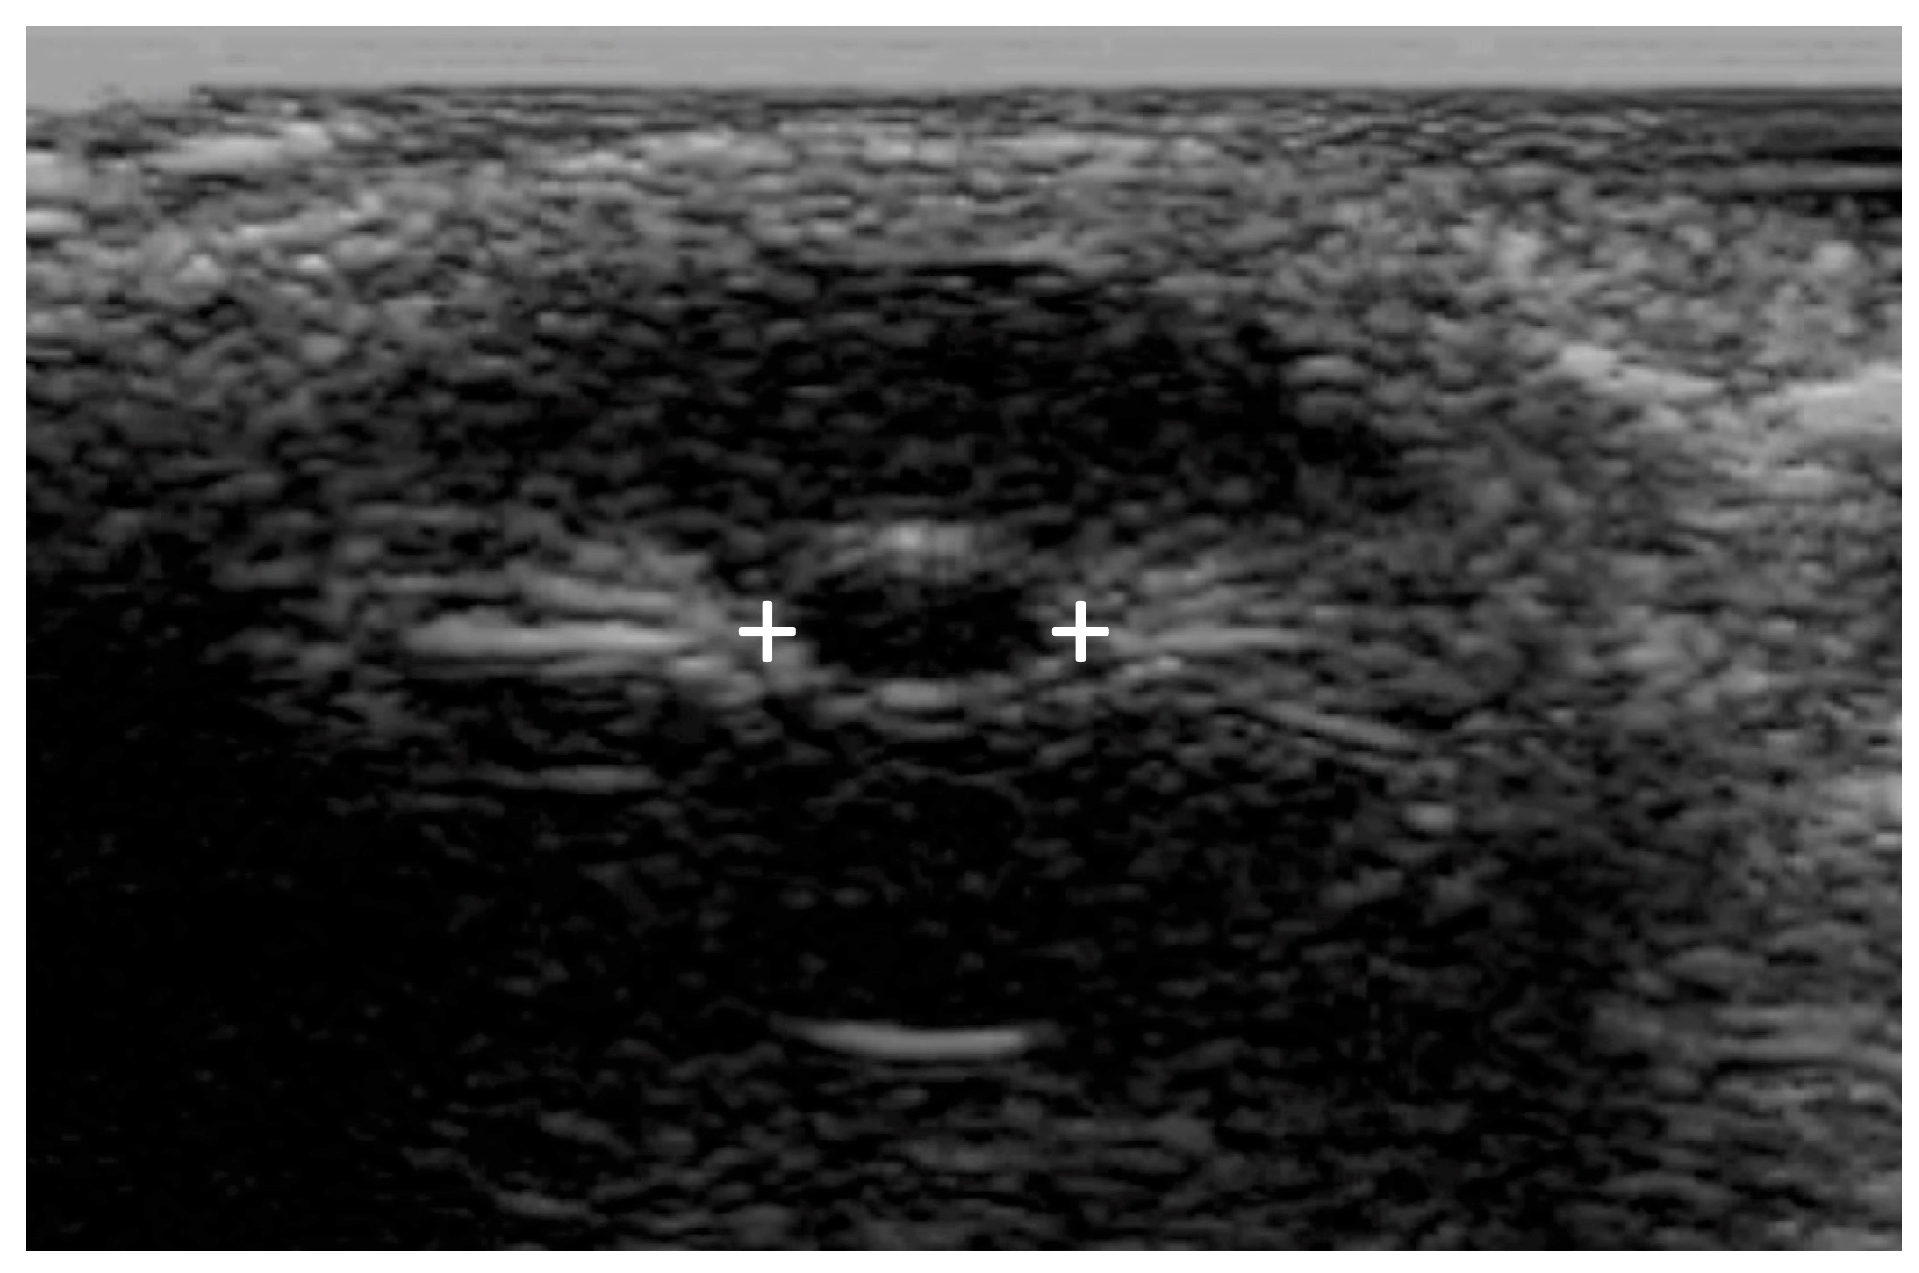

Commercially available PAIPs lack the capability for bilateral observation, rendering the assessment of relative afferent defects impossible. Furthermore, the use of currently available commercial PAIPs with fixed light intensity and duration may affect the sensitivity of the examination. Finally, agitated or confused patients as well as patients with scleral or periorbital edema, intraocular lens replacement, or prior ocular surgical procedures can be difficult to evaluate [77,78]. Ultrasound pupillometry can be applied in some cases [79] of facial or orbital trauma, but there are currently no automated portable devices offering standardized ultrasound measurements (Figure 4).

Figure 4.

Bedside or portable ultrasound can be used to assess the pupillary reactivity when one or both eyes cannot be opened. Pupillary size is indicated by the plus signs.